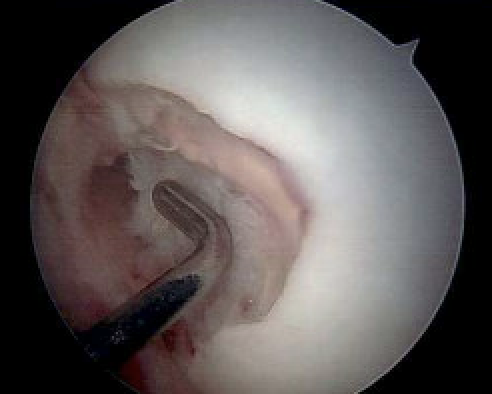

Arthroscopy and fragment removal

Small irreparable chondral fracture from central patella